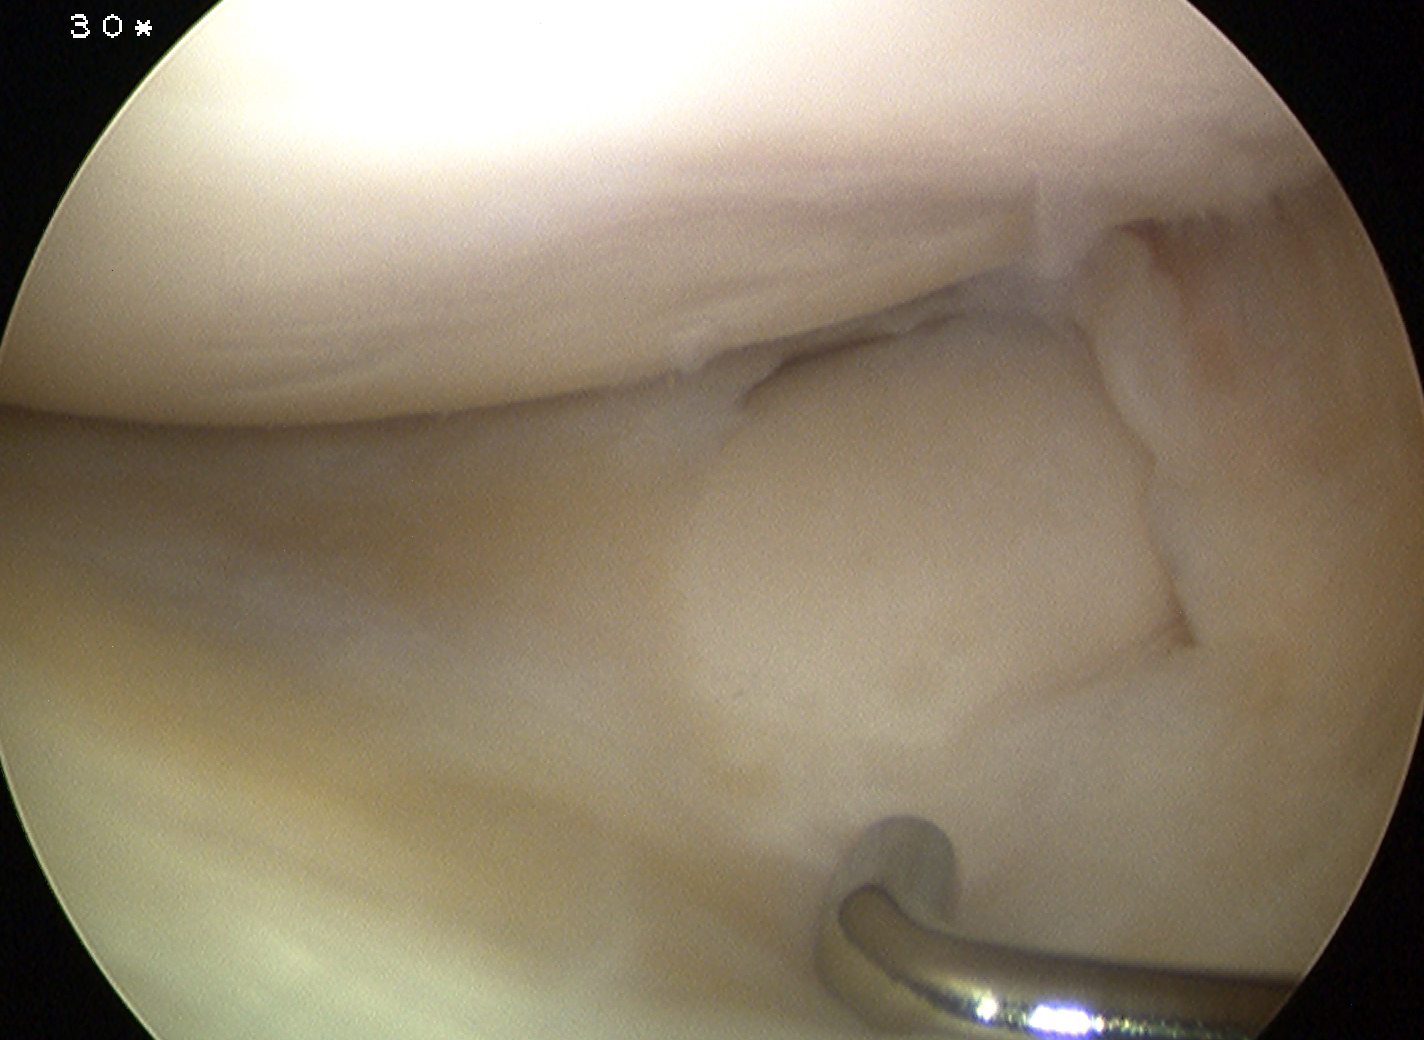

Aim

Convert unstable meniscus to a stable contoured one

Options

1. Stable

- partial central meniscectomy / saucerisation

2. Unstable (Wrisberg type)

- posterior capsular stabilisation / repair +/- saucerisation

Ahn et al Arthroscopy 2008

- 23 patients treated with posterior repair and partial central meniscectomy

- no reoperation at 51 months

- good symptomatic relief